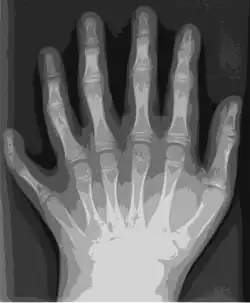

Imagen original en JPEG (891×1,077 p, 119 KB) -